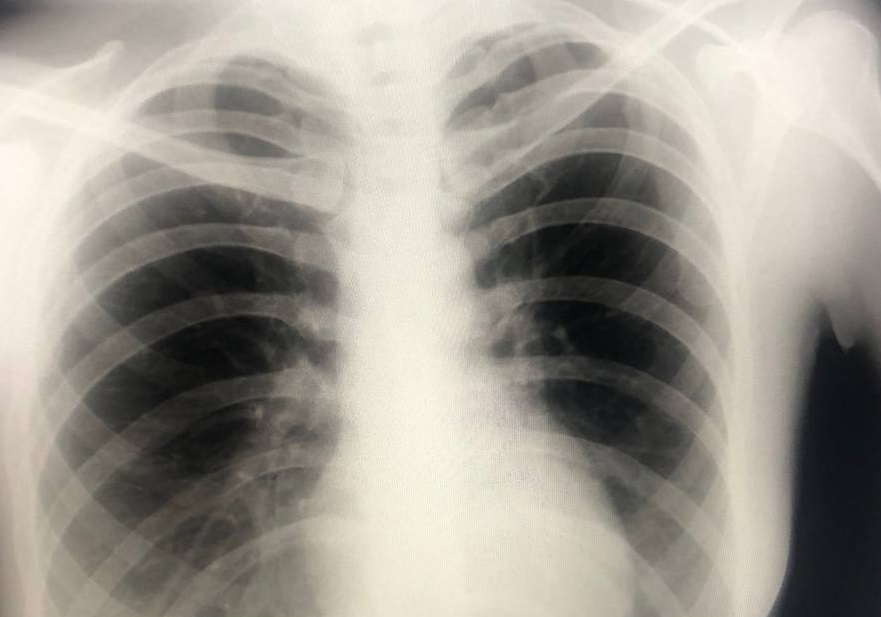

«Флюорография остается самым информативным методом ранней диагностики туберкулеза и патологий органов дыхания. Скрининг безопасен для организма, так как лучевая нагрузка минимальна. Для контроля состояния здоровья достаточно проходить это обследование один раз в год», — подчеркнул исполняющий обязанности заведующего рентгеновским отделением Няганской городской поликлиники Глеб Садовский.